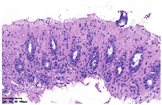

UC始于直肠,常见左半结肠,以直肠、乙状结肠为重,病变向近端结肠逐渐减轻。炎症呈连续性、弥漫性分布,病变不同部位活检均可见程度相近的慢性肠炎,炎症分布均匀,炎症程度及隐窝结构改变程度较为一致。黏膜固有层全层可见大量淋巴细胞、浆细胞浸润,隐窝结构改变广泛而显著,可见基底浆细胞增多,潘氏细胞化生,结肠黏膜表面绒毛化,见图10。